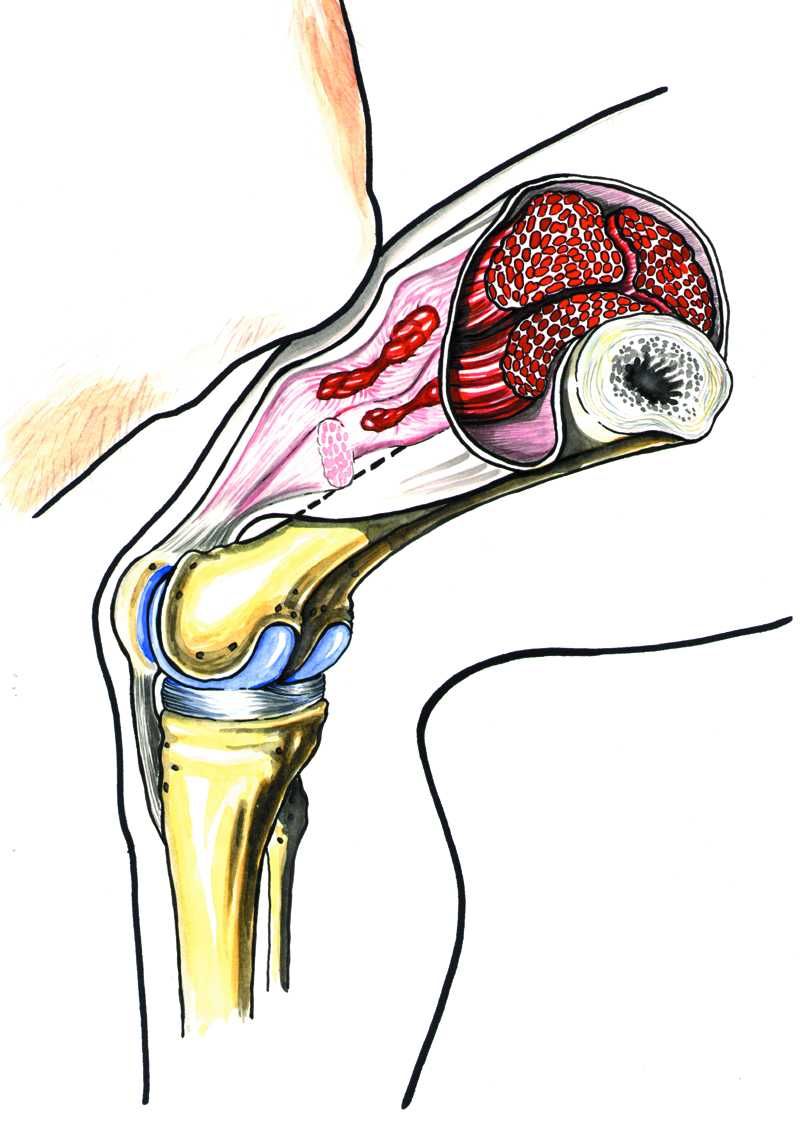

«Lårhøne»

De fleste har vel hørt uttrykket «lårhøne». En «lårhøne» er nettopp en slik skade på framsiden av låret, som fører til at blodkar under huden blir sprengt. Slike skader kan gi varige men hvis de får mangelfull eller feil behandling.

Det er forskjell på om blødningen blir stengt inne i en enkelt muskel, eller om blodet får fordele seg over et større område. Ved en «lårhøne» kan blodet for eksempel lekke inn i vevene nedover mot kneet. De alvorligste skadene er de intramuskulære, der blodet blir stengt inne i muskelen.